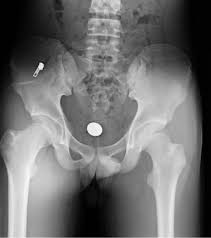

Anterior Superior Iliac Spine, Appendicular Skeleton And Joints Ppt Download : It can be palpated by putting the hands at the top of the hipbones and following the bony margins toward the front of the hips.. The posterior border of the ala, shorter than the anterior, also presents two projections separated by a notch, the posterior superior iliac spine and the posterior inferior iliac spine. Jun 28, 2021 · insertion: Asis, anterior superior iliac spine. Diagnosis is made with pelvis radiographs that shows an avulsion off the aiis. Anterior angulation of the coccyx may be a normal variant but poses a diagnostic challenge for those considering coccygeal trauma.

It provides attachment for the inguinal ligament , the sartorius muscle , 1 4 and the tensor fasciae latae muscle. The anterior superior iliac spine (asis) is the most anterior part of the iliac crest. An anterior superior iliac spine (asis) avulsion is a traumatic avulsion of the asis due to a sudden and forceful contraction of the sartorius and tensor fascia lata that occurs in young athletes. Asis, anterior superior iliac spine. This part is the most observable and palpable of the pelvis. The posterior border of the ala, shorter than the anterior, also presents two projections separated by a notch, the posterior superior iliac spine and the posterior inferior iliac spine. Diagnosis is made radiographically with displaced injuries but ct/mri may be required to diagnosis nondisplaced fractures. It provides attachment for the inguinal ligament, and the sartorius muscle. An anterior inferior iliac spine (aiis) avulsion is an apophyseal avulsion injury seen in adolescent athletes as a result of eccentric contraction of the rectus femoris. It refers to the anterior extremity of the iliac crest of the pelvis. The anterior superior iliac spine refers to the anterior extremity of the iliac crest of the pelvis. Outer lip of anterior iliac crest, anterior superior iliac spine (asis) insertion: Classification four types of coccyx have been described:

Outer lip of anterior iliac crest, anterior superior iliac spine (asis) insertion: Aug 29, 2017 · aiis, anterior inferior iliac spine; Asis, anterior superior iliac spine. The posterior border of the ala, shorter than the anterior, also presents two projections separated by a notch, the posterior superior iliac spine and the posterior inferior iliac spine. An anterior superior iliac spine (asis) avulsion is a traumatic avulsion of the asis due to a sudden and forceful contraction of the sartorius and tensor fascia lata that occurs in young athletes. The tensor fasciae latae and sartorius muscles of the thigh have their origins at the anterior superior spine. An anterior inferior iliac spine (aiis) avulsion is an apophyseal avulsion injury seen in adolescent athletes as a result of eccentric contraction of the rectus femoris. It provides attachment for the inguinal ligament, and the sartorius muscle. The posterior superior iliac spine serves for the attachment of the oblique portion of the posterior sacroiliac ligaments and the multifidus. It provides attachment for the inguinal ligament , the sartorius muscle , 1 4 and the tensor fasciae latae muscle. It can be palpated by putting the hands at the top of the hipbones and following the bony margins toward the front of the hips. Classification four types of coccyx have been described: Diagnosis is made radiographically with displaced injuries but ct/mri may be required to diagnosis nondisplaced fractures.